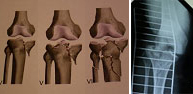

La articulación de la rodillacompromete los extremos inferior del fémur y superior de la tibia. Además se encuentran implicadas las estructuras ligamento-meniscales de esta región lo que hace de su tratamientouno de los más complejos del esqueleto. Las lesiones óseas a este nivel son producidas por traumatismos de alta energía, desde accidentes de tráfico y caídas desde gran altura hasta deportes como fútbol, rugby, artes marciales, deportes de motor, esquí, etc. El enorme abanico de lesiones a este nivel requiere de un estudio detallado antes de tomar decisiones de tratamiento. Los últimos avances en técnica artroscópica han permitido la realización del tratamiento a través de heridas de mínimo tamaño por las que se introduce una cámara óptica permitiendo la reparación de la lesión bajo visión directa en una pantalla.